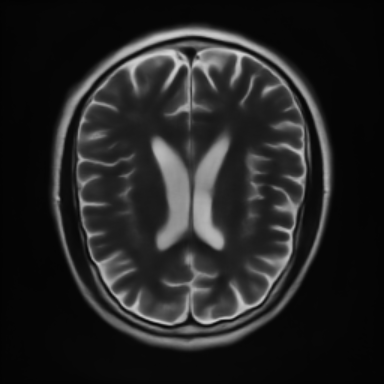

This article presents a novel undersampled magnetic resonance imaging (MRI) technique that leverages the concept of Neural Radiance Field (NeRF). With radial undersampling, the corresponding imaging problem can be reformulated into an image modeling task from sparse-view rendered data; therefore, a high dimensional MR image is obtainable from undersampled $k$-space data by taking advantage of implicit neural representation. A multi-layer perceptron, which is designed to output an image intensity from a spatial coordinate, learns the MR physics-driven rendering relation between given measurement data and desired image. Effective undersampling strategies for high-quality neural representation are investigated. The proposed method serves two benefits: (i) The learning is based fully on single undersampled $k$-space data, not a bunch of measured data and target image sets. It can be used potentially for diagnostic MR imaging, such as fetal MRI, where data acquisition is relatively rare or limited against diversity of clinical images while undersampled reconstruction is highly demanded. (ii) A reconstructed MR image is a scan-specific representation highly adaptive to the given $k$-space measurement. Numerous experiments validate the feasibility and capability of the proposed approach.